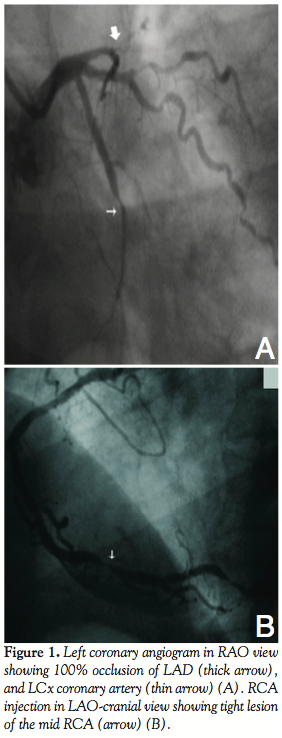

Coronary angiogram from right radial approach showed normal left main; 100% occlusion of LAD just after the first septal branch; 100% proximal occlusion of left circumflex artery (Figure 1A); and 90% discrete lesion of RCA with multiple disease of the posterior left ventricular branch (Figure 1B). The patient underwent percutaneous coronary angioplasty from right radial approach.